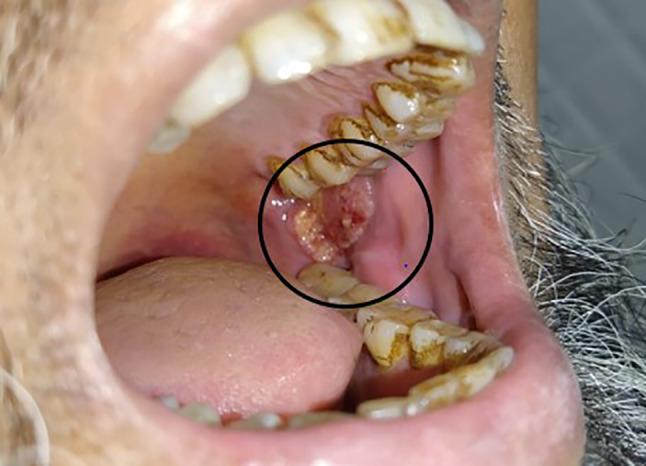

Early retromolar trigone (RMT) lesions are difficult to access and free tissue transfer is often an overkill for such small lesions. The aim was to devise a novel surgical approach that would aid the resection without raising a cheek flap and simultaneously provide a local reconstructive option for small lesions in the RMT.

This study was to demonstrate the outcomes of the "trans-facial" approach used to simultaneously access and reconstruct small RMT tumors through an islanded nasolabial flap. Patients with histologically proven squamous cell carcinoma of RMT requiring surgery were included from January 2021 to September 2022. Case selection was done based on the location of the disease and its size (cT1/T2). All needed bone and soft tissue resection via per oral trans-facial approach, along with an ipsilateral neck dissection. The technique is described along with their post-operative and pathologic outcomes.